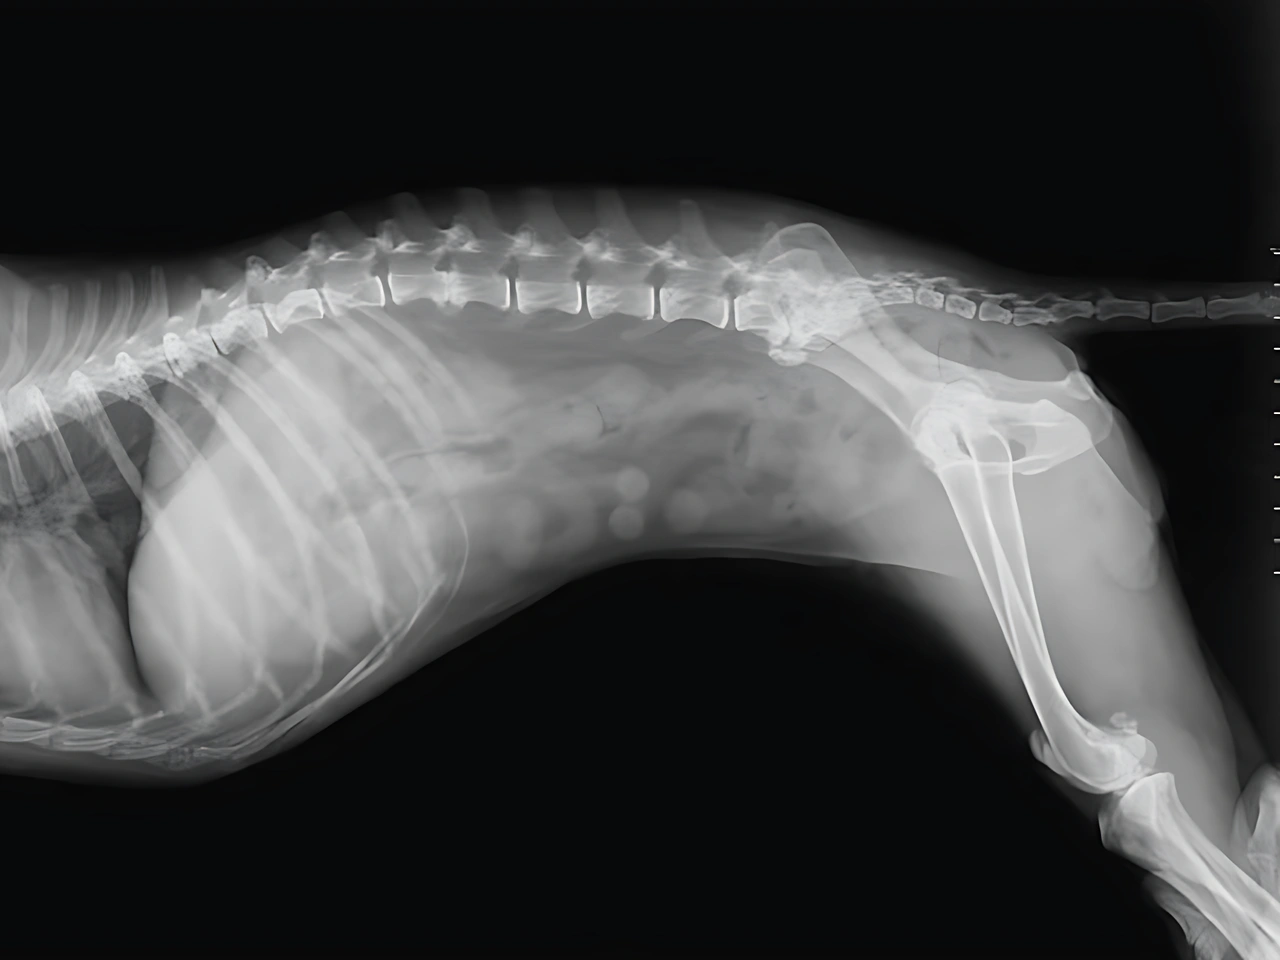

Does your dog need an X-ray, and you’re unsure what to expect? In veterinary medicine, X-rays are commonly used by veterinarians as a diagnostic tool to examine your dog’s chest, abdomen, or limbs. Vets use state-of-the-art diagnostic imaging tools to detect conditions that aren’t visible on the surface.

Your veterinarian may recommend an X-ray to check for broken bones, bladder stones, foreign bodies, or fluid in the lungs. Sedation may be required to keep your dog calm during the x-ray procedure, especially if stillness is necessary for a clear x-ray. In some cases, imaging such as ultrasound could also be used to examine soft tissue or abdominal organs more closely.

X-rays help provide an accurate diagnosis by revealing tissue densities, internal organs, and areas of concern within the dog’s body. The use of X-ray technology allows veterinary clinics and animal hospitals to better understand your dog’s condition. Keep reading to learn how veterinarians explain the procedure, when sedation may be used, and how diagnostic x-rays play a vital role in your dog’s health.

How X-Rays Work and What They Reveal

Veterinary clinics frequently use X-rays to explore different areas of the body:

- An X-ray machine sends an X-ray beam through the body to capture images.

- Tissues absorb some X-rays depending on their density; the cranium absorbs all X-rays, creating a clear contrast.

- X-rays are captured on X-ray film or as a digital X-ray, depending on the technology used.

- These images help detect issues such as broken bones, foreign objects, enlarged organs, or fluid buildup.

Since radiation is involved, the procedure is done quickly and safely, often while the dog is calm or gently restrained.

X-rays play a key role in veterinary care by helping veterinarians see inside a dog’s body without surgery. They are especially useful when a dog shows signs of illness or injury that aren’t visible from the outside.

- X-rays are fast, non-invasive tools that allow veterinarians to examine a dog’s bones, joints, and internal organs.

- They help detect conditions such as broken bones, bladder stones, tumours, and swallowed foreign objects.

- X-Rays can reveal problems in the lungs, heart, and abdomen that can’t be seen through physical exams alone.

- Veterinarians use X-Ray technology to glean information about soft tissue and tissue densities.